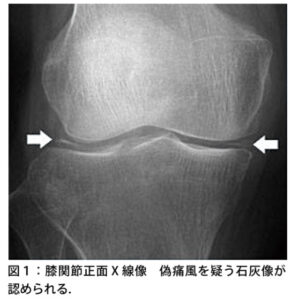

| X線所見 | 石灰化像なし | 石灰化像あり |

| 検査 | 【血液検査】 55歳未満の場合は二次性(4H)を否定するためCa、P、Fe、Mg、ALPを確認 【画像検査】単純X線:関節軟骨の線状石灰化像、関節裂隙に層状石灰化 ※画像所見があっても結晶誘発性関節炎と診断できるだけでCPPD症とは限らない エコー:膝関節の硝子軟骨内に石灰化を認めればCPPD症を疑う頸部CT:crowned dens syndromeの場合、軸椎歯突起後方の環椎横靱帯の石灰化所見が見える。 【関節穿刺】 急性期に穿刺し、関節液を偏光顕微鏡で観察し、方形・棒状の結晶を確認(確定診断) ※ただし、化膿性関節炎や関節リウマチなどに合併することもあるため慎重に診断すべし |

【画像検査】

エコー:膝関節の硝子軟骨内に石灰化を認めればCPPD症を疑う